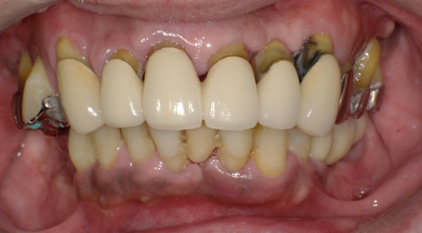

術後の写真です。フレアーアウトした分、歯を引っ込めてかみ合わせも若干高くしています。

術前の口元と別人になっているのが分かると思います。

オールオンフォーの良いところはこのように好きなように歯を並べることができることです。

欠点は清掃が難しいこと、ネジ式なのでネジの穴の部分に仮の蓋をつけないといけないので少し審美が劣るところです。